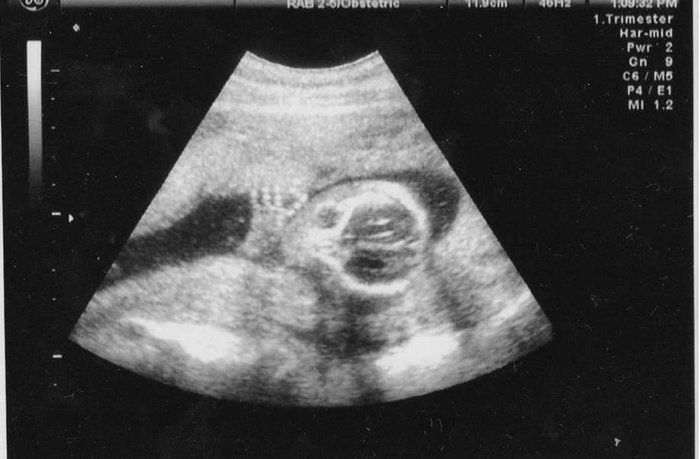

犬飼ねこさんの妊娠18週目のエコー写真

頭の骨がしっかりしてきました。ムンクの叫びのよう。